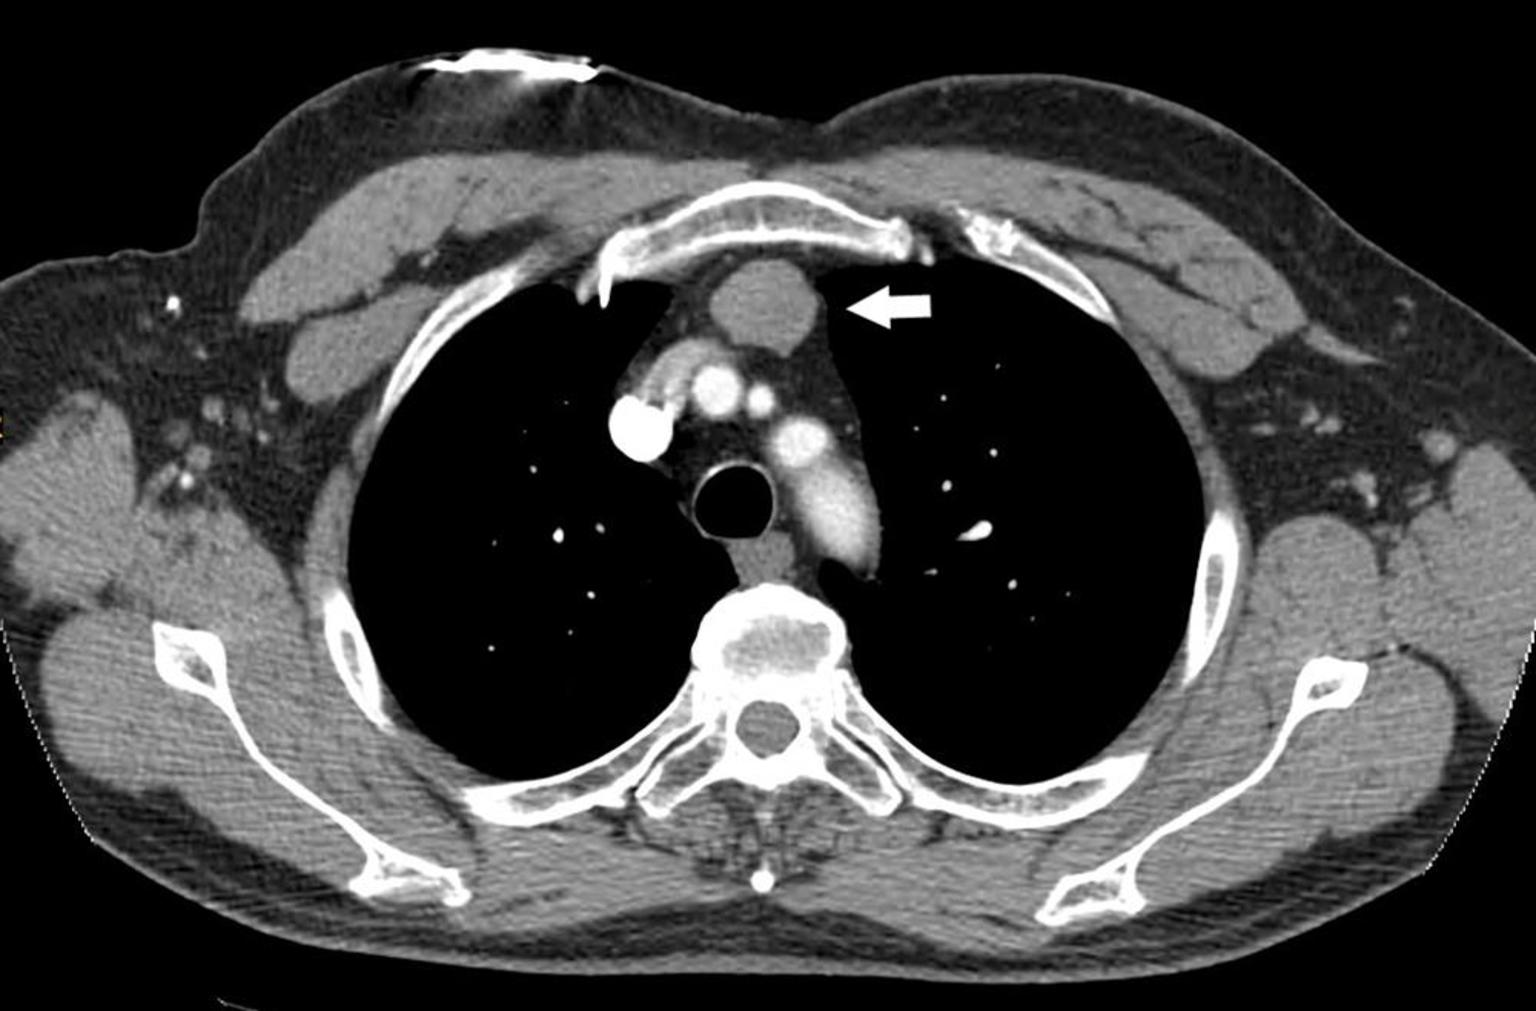

成功运用ct引导下右肺及纵隔肿瘤碘-125粒子植入术,为一名罕见nut癌

箭头所指为巨大纵隔肿瘤